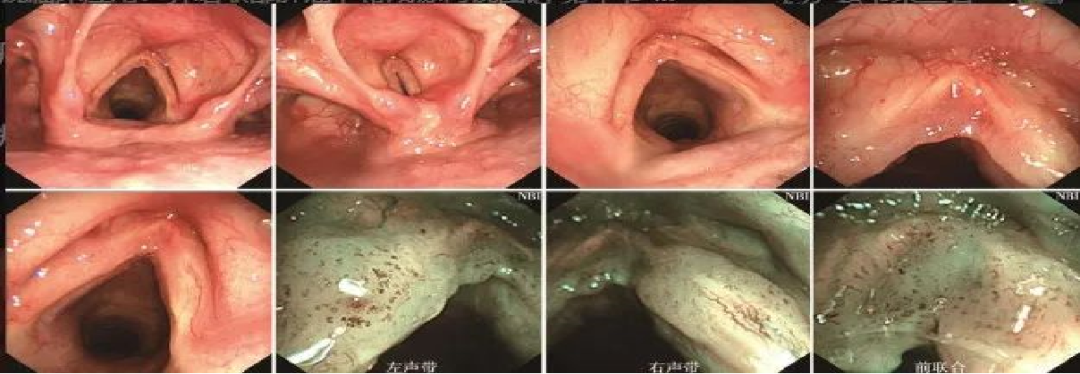

声门型喉癌

A.外院喉镜检查发现右侧声带中部白斑,未取活检,性质难定;

B、C.声门区右侧声带中部可见白斑(活检4块),白斑周围黏膜充血;

D.NBI模式下可见白斑周围充血处黏膜有明显的斑点状表现。